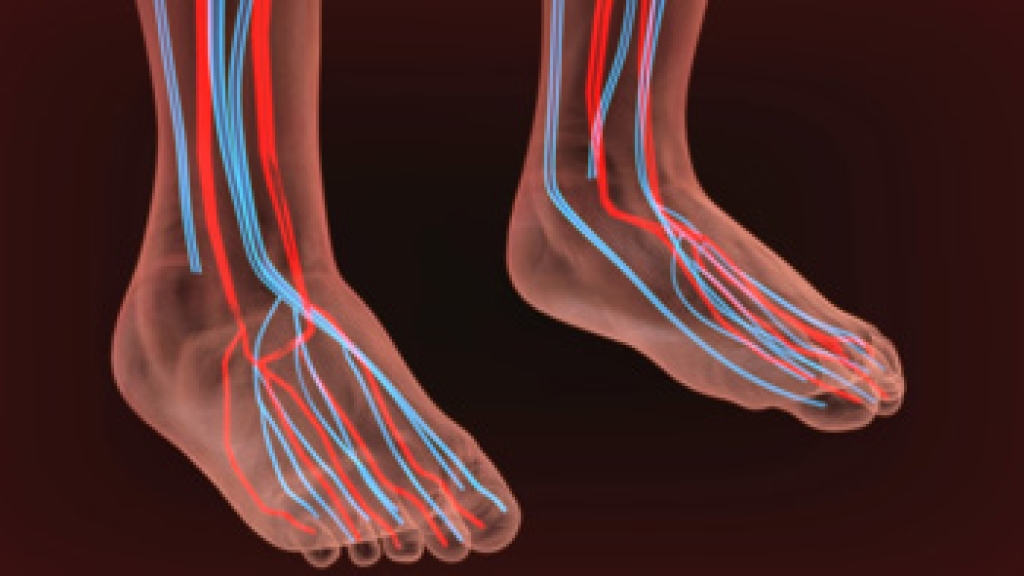

Wound care is the practice of taking proper care of a wound. This can range from the smallest to the largest of wounds. While everyone can benefit from proper wound care, it is much more important for diabetics. Diabetics often suffer from poor blood circulation which causes wounds to heal much slower than they would in a non-diabetic.

While it may not seem apparent with small ulcers on the foot, for diabetics, any size ulcer can become infected. Diabetics often also suffer from neuropathy, or nerve loss. This means they might not even feel when they have an ulcer on their foot. If the wound becomes severely infected, amputation may be necessary. Therefore, it is of the upmost importance to properly care for any and all foot wounds.